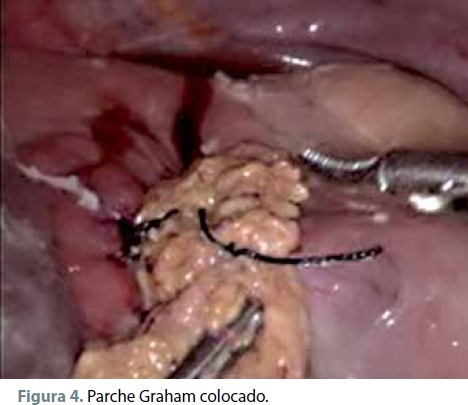

Posteriormente se colocó un parche de epiplón mayor (ligamento gastrocólico) sobre la zona de la úlcera, anudando progresivamente de superior a inferior los cabos libres de cada una de las hebras cubriendo totalmente dicha área (figura 4).